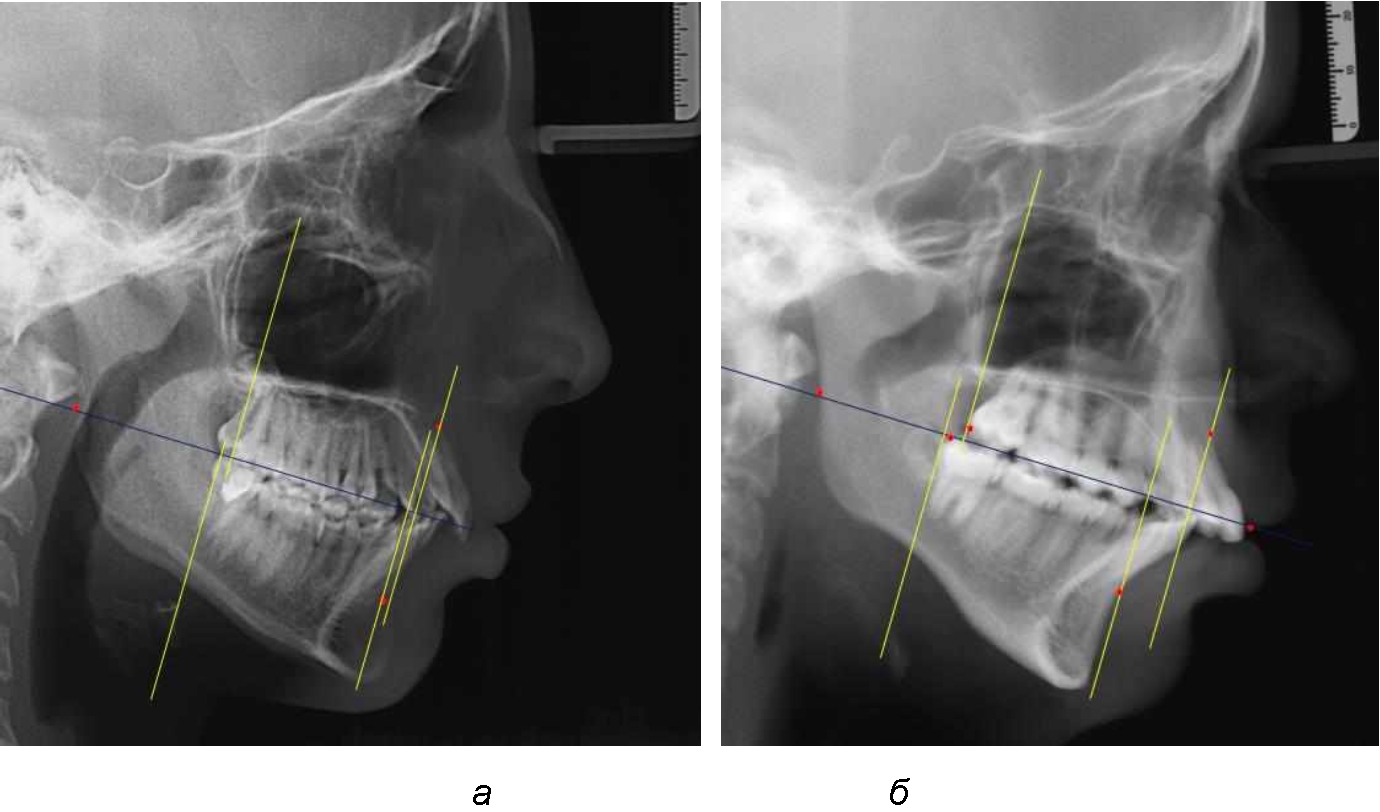

Аналогичное расстояние было отмечено и при расположении дистальных окклюзионных точек верхней и нижней челюсти (рис. 2).

Рис. 2. Положение апикальных точек и челюстей при нормопозиции (а), антепозиции (б) и ретропозиции (в) верхней челюсти

При анализе рентгенограмм, было отмечено, что на 26 снимках из 58 [(44,83 ± 6,53) %] отмечалась нормопозиция верхней челюсти. При этом средняя величина лицевого угла (ANSe) составила (85,04 ± 0,56)°, и пациенты были отнесены к 1-й группе 1-й подгруппе. Антепозиция верхней челюсти была отмечена на 20 те-лерентгенограммах [(34,483 ± 6,24) %], при этом величина лицевого угла составляла (89,12 ± 0,62)°. Ретропозиция была отмечена на 12 рентгенограммах [(20,69 ± 5,32) %], а средняя величина лицевого угла составляла (80,21 ± 0,48)°.

При всех вариантах положения верхней челюсти, было отмечено, что альвеолярно-денталь-ные размеры верхних зубо-челюстных дуг были близки по значению к аналогичным размерам нижней челюсти и разница в размерах не превышала 1,0–1,5 мм, а средняя величина различия показателей составляла (1,07 ± 0,54) мм.

Расстояние от конструируемой точки окклюзионной плоскости на ветви челюсти («rmРOcP») до апикальных точек Downs на обеих челюстях также коррелировало между собой, и средняя величина различия показателей составляла (1,23 ± 0,69) мм. Проекция нижней апикальной точки на окклюзионную линию, как правило, располагалась несколько кпереди проекции верхней апикальной точки, на величину около 1 мм, что соответствовало оптимальным данным Wits-анализа.